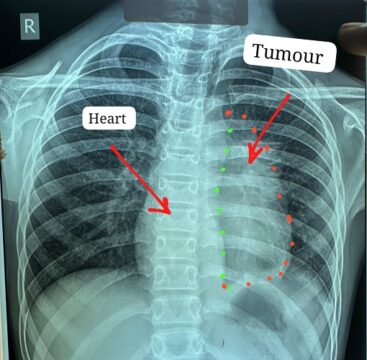

विभाग की टीम ने 11 वर्ष के एक बच्चे के हृदय से चिपके अत्यंत दुर्लभ स्टेज-3 इनवेसिव थायमिक कैंसर (टाइप-बी थायमोमा) का सफल ऑपरेशन कर विश्व स्तर पर नया कीर्तिमान स्थापित किया है।

यह ट्यूमर हृदय, पेरिकार्डियम, फ्रेनिक नर्व महाधमनी (एओर्टा), मुख्य पल्मोनरी आर्टरी, लेफ्ट एट्रियम और फेफड़े से चिपका हुआ था। ऐसे मामलों में ट्यूमर को पूरी तरह निकाल पाना (आर-0 रिसेक्शन) लगभग असंभव माना जाता है, लेकिन अस्पताल में उपलब्ध हार्ट-लंग मशीन की मदद से यह संभव हो पाया।

मुख्य ट्यूमर के अलावा फेफड़े की प्लूरल कैविटी में फैले तीन अन्य सैटेलाइट ट्यूमर को भी सावधानीपूर्वक निकाला गया, ताकि भविष्य में कैंसर दोबारा फैलने की संभावना न रहे। निकाले गए ट्यूमर का आकार लगभग 12×8 सेंटीमीटर और वजन करीब 400 ग्राम था।

Big Cancer Operation Sucssefully Done at JNM: चांपा निवासी कक्षा छठवीं में पढ़ने वाले इस बच्चे को करीब छह महीने से छाती में दर्द, भारीपन और सांस फूलने की शिकायत थी। जांच में पता चला कि उसके सीने में बड़ा ट्यूमर है, जो हृदय और मुख्य धमनियों से चिपका हुआ है। प्रदेश के कई अस्पतालों में ऑपरेशन से मना किए जाने के बाद मरीज को अम्बेडकर अस्पताल भेजा गया।